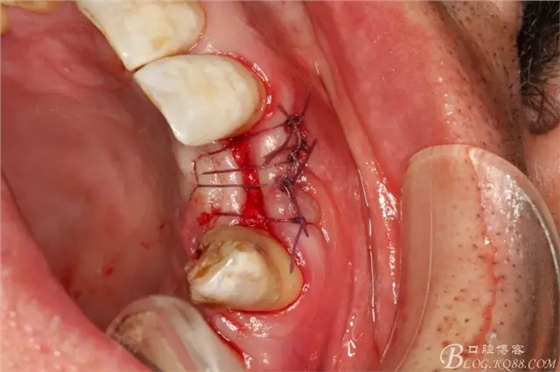

圖6.切開、翻瓣、清理牙槽嵴骨面上的纖維結(jié)締組織。

圖7.植入種植體。奧齒泰:直徑3.5mm。長度11.5mm。

圖8.植體頰側(cè)有約2mm間隙,植入bicon骨粉。

圖9.表面覆蓋膠原蛋白海綿

圖10.縫合